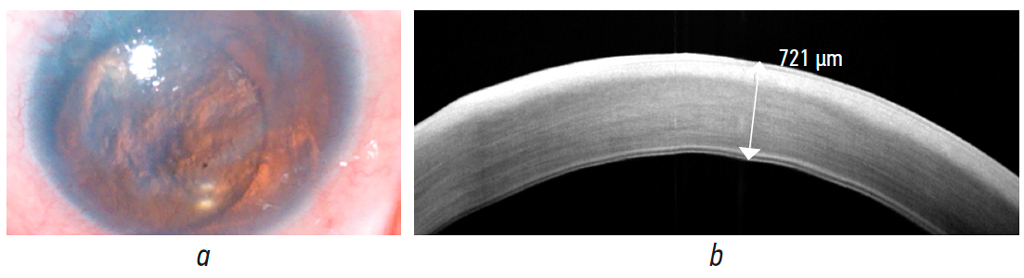

A 52-year-old female patient with congenital aniridia had bilateral lens-iris diaphragm implantation with cataract removal 20 years ago. After 1 year, secondary glaucoma required bilateral lens-iris diaphragm removal with implantation of a posterior chamber IOL in the left eye. She was followed-up in the Kaluga Branch of the Fyodorov Eye Microsurgery Federal State Institution over the past 5 years. At presentation, OS subclinical corneal edema was observed, central corneal thickness was 598 μm, and BCVA was 0.2. In 2022, OS bullous keratopathy, decreased vision, anterior dislocation of the posterior chamber IOL, and IOL contact with the posterior corneal surface (Fig. 2, a) required endothelial keratoplasty with IOL explantation. To prevent the endothelial graft migration into the vitreous cavity and air migration into the posterior segment, modified posterior lamellar keratoplasty using a BSF was performed.

Fig. 2. Clinical case 2: a, photo of the anterior segment of the eye before surgery, aniridia, bullous keratopathy, intraocular lens dislocation; b, OCT of the cornea before surgery, central thickness of the cornea is 721 µm

Рис. 2. Клинический случай № 2; a — фото переднего отрезка глаза перед операцией, аниридия, буллёзная кератопатия, дислокация интраокулярной линзы; b — ОКТ роговицы до операции, центральная толщина роговицы 721 мкм

Pre-operative uncorrectable visual acuity was 0.05, IOP was 21 mmHg, with hypotensive therapy, OCT revealed central corneal thickness of 721 μm (Fig. 2, b). ECD was not determined.